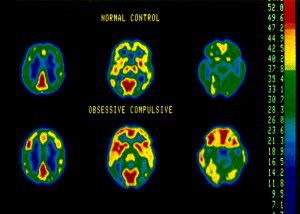

Il disturbo è correlato a una disfunzione del neurotrasmettitore serotonina, che viene stimolata dall’iperattività del giro del cingolo anteriore, del nucleo caudato e del circuito orbito frontale. Viene curato quindi, con degli inibitori per la serotonina.